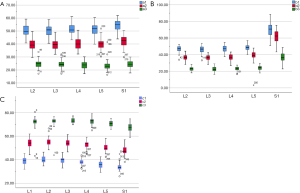

The angles of each path (Table 2)

Full table

The included angles a1, a2, a3, b1, b2, b3 and c1, c2 and c3 in the sagittal plane were significantly different (P≤0.001) (Figure 13) (a1 > a2 > a3, b1 > b2 > b3, c1 < c2 < c3). In the angles of sagittal down-path, b1, b2 and b3 change significantly and consistently, showing a trend of decreasing first and then increasing, which is the smallest at L3 (46.08±4.37°, 36.21±3.51°, 22.47±3.01°) and the largest at S1 (69.49±8.28°, 61.23±7.74°, 36.60±5.00°). In the angles of sagittal up-path, a1 and a2 change in the same way, showing an increasing trend. While a3 goes down and then goes up, which is the smallest at L4 (23.43±4.29°) and the largest at L5 (24.36±2.94°). In the angles of axial plane, c1, c2 and c3 change in the same way, showing a trend of increasing first and then decreasing. c1 and c2 are the largest at L2 (40.07±2.75°, 55.1±3.32°), and c3 is the largest at L3 (73.11±2.10°). c1, c2 and c3 are the smallest at S1 (33.87±2.94°, 47.92±3.54°, 67.15±3.60°) (Figures 14,15).